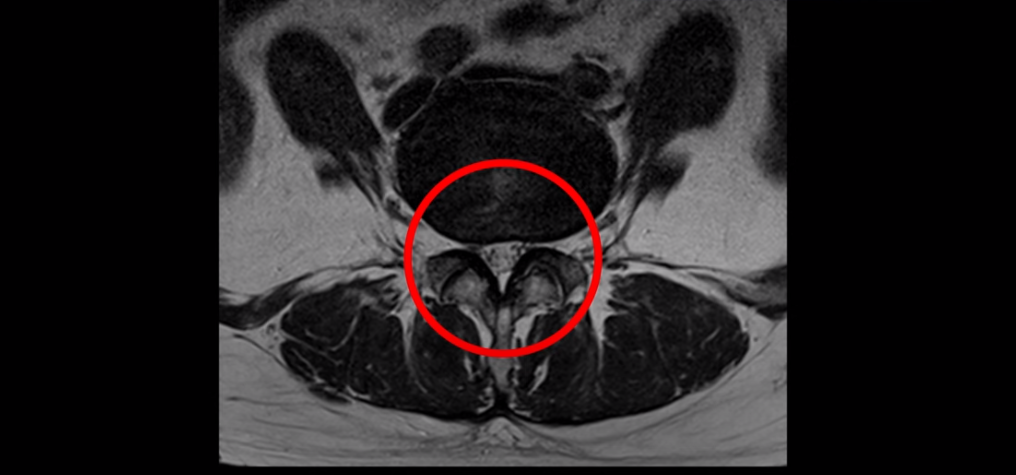

이분 MRI를 보면 여러 마디가 퇴행이 진행되어 있고

3번 4번과 4번 5번에 중심성 협착이 있는데

4번 5번이 더 심합니다.

또 4번 5번 마디에 오른쪽으로 찢어져서 밀려나온 디스크 탈출이 보입니다.

밀려나온 수핵이 조금 흘러내려 있습니다.